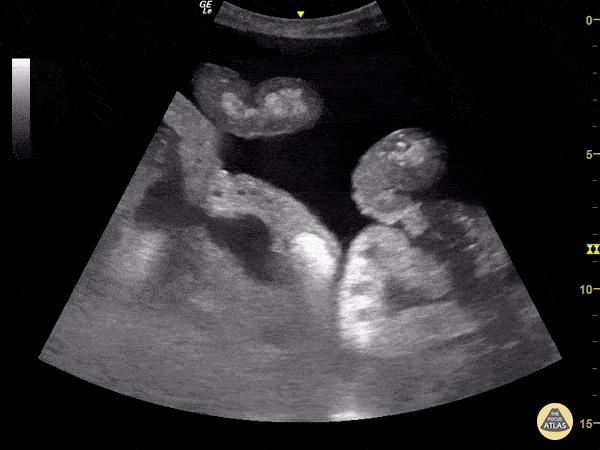

70-year-old man with a history of alcoholic liver cirrhosis. Using a curvilinear probe on the left lower quadrant we appreciate significant ascites; also note the clear outline of bowel loops floating within the free abdominal fluid. Renato Tambelli, Emergency Physician Hospital das Clínicas de Marília.Public Healthcare. Emergency Management. @R_Tambelli